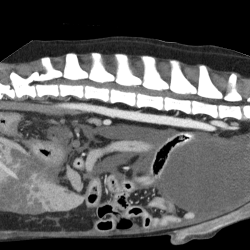

健康的な食生活を送るために欠かせない「口腔・歯」に関しての診察を行います。

多くのワンちゃんネコちゃんが「歯周病・歯肉炎」を患っていると言われています。

重度の歯周病や歯肉炎になると、大好きなご飯も食べられなくなり、歯がぐらつき、抜け落ちてしまう恐れもあります。歯石には多くの細菌が住み着いており、「歯石は多くの病気の原因になる」と言われています。健康的な生活に欠かせない「口腔・歯のケア」を心がけましょう。歯周病

歯周ポケット(歯と歯茎の間)に入り込んだ細菌が増殖して、歯や歯茎に炎症を起こしている状態を「歯肉炎」と言います。

さらに病態が進行し、「歯のぐらつき・歯茎からの出血・歯茎の後退」といった症状を総称して「歯周病」と呼びます。

歯磨きの習慣がないワンちゃんやネコちゃんは、多くが「歯周病」を患っています。重度歯周病

「歯周病」が歯根にまで及ぶと、歯を抜く処置が必要になる場合もあり、放置しておくと顎の骨を溶かしてしまう恐れもあります。

さらには「歯周病菌」が歯茎の血管から侵入し、全身を巡る事によって、心臓や腎臓といった臓器にも悪影響を及ぼします。歯石

歯石とは歯の表面に付いた歯垢(プラーク)で細菌が繁殖し、唾液などに含まれるミネラルによって歯垢が硬化したものです。

歯垢は歯の表面に付着した汚れの事で、歯磨きによって取り除く事が可能です。しかし一度歯石になってしまうと歯磨きでは取り除く事が出来ません。また歯石の表面はデコボコしているため、歯垢がより付着しやすくなり、更に歯石が出来やすくなるという悪循環に陥ります。

歯石をきれいに取り除くためには、で全身麻酔をかけて歯石除去(スケーリング)をする必要があります。スケーリング(歯石除去)

歯の表面に付いた歯石を特殊な機械を用いて除去する事を「スケーリング」と言います。

歯石を除去した後に歯の表面を研磨剤で磨くことで表面を滑らかにします。そうする事で歯垢が付きにくくなり、付着を予防する事が出来ます。歯石除去を行ったからといって、ずっと歯石が付かなくなる訳ではありません。

症状:口臭 歯石 食べる時に痛がる 頬の腫れ くしゃみがでる など

これらの症状が認められた時は、歯肉炎や歯周病など、様々な口腔内トラブルが考えられます。

人間と同じように、犬・猫も定期的な歯科検診を受ける事をお勧めします。

歯周病を防ぐ為にも、口腔内のケアも重要です。様々なデンタルグッズもあるので、治療前後のケアも心がけましょう。神経科